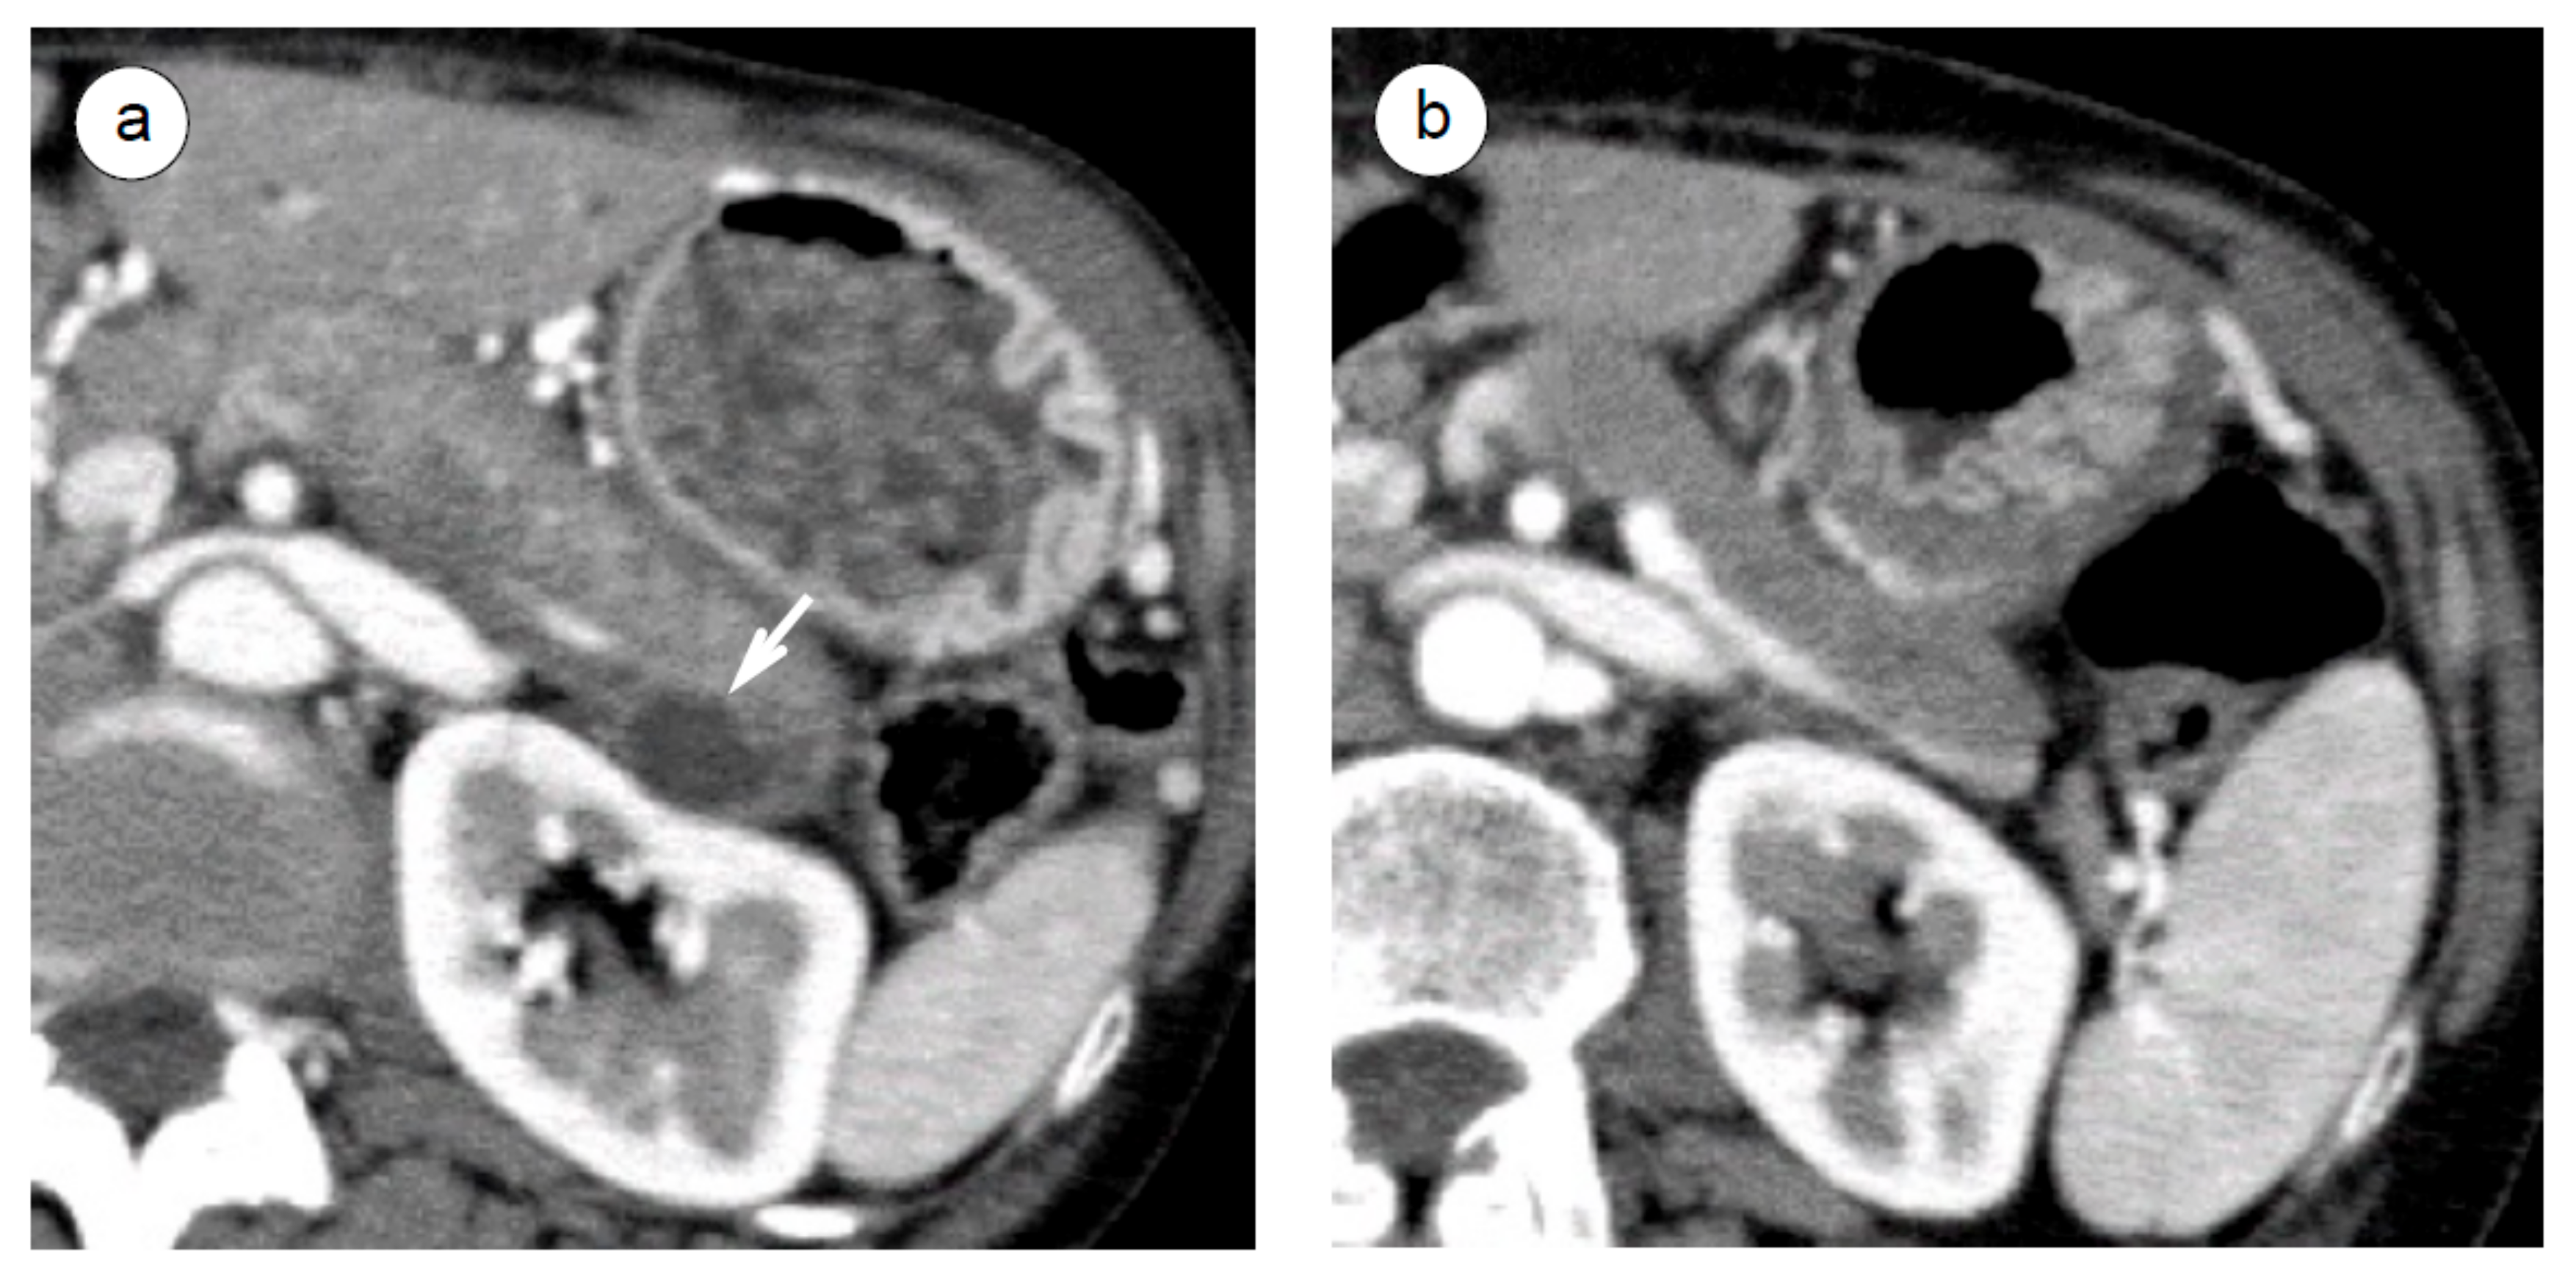

- Matsubayashi, H.; Iwai, T.; Matsui, T.; Wada, T.; Kawata, N.; Ito, H.; Sasaki, K.; Uesaka, K.; Ono, H. Pancreatic cystic lesions with atypical steroid response should be carefully managed in cases of autoimmune pancreatitis. J. Gastroenterol. Hepatol. 2016, 31, 270–276. [Google Scholar] [CrossRef]

- Kubota, K.; Fujita, Y.; Sato, T.; Sekino, Y.; Hosono, K.; Kobayashi, N.; Fujisawa, N.; Kagawa, K.; Fujisawa, T.; Matsuhashi, N.; et al. Autoimmune pancreatitis associated with pancreatic cyst: How can we manage it? J. Hepatobiliary Pancreat. Sci. 2014, 21, 902–910. [Google Scholar]

- Kuraishi, Y.; Watanabe, T.; Muraki, T.; Ashihara, N.; Ozawa, M.; Nakamura, A.; Kanai, K.; Hamano, H.; Kawa, S. Effectiveness of steroid therapy for pancreatic cysts complicating autoimmune pancreatitis and management strategy for cyst-related complications. Scand. J. Gastroenterol. 2019, 54, 773–779. [Google Scholar]

- Matsubayashi, H.; Kubota, K. Pancreatic Cystic Lesions in Cases of Autoimmune Pancreatitis. Pancreas 2019, 48, e14. [Google Scholar]